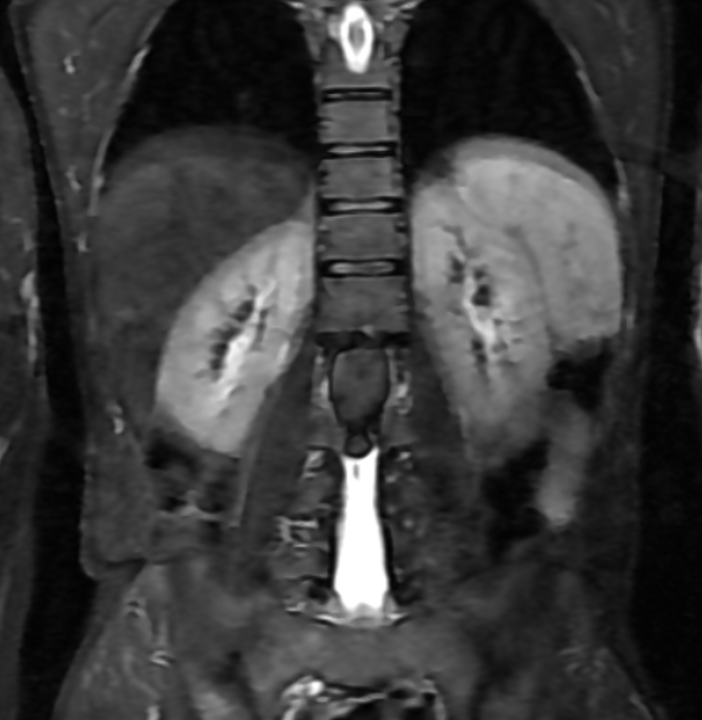

CORONAL T2 STIR

MRI is the modality of choice for evaluation of spinal epidermoid cysts. Although classically described as T1 hypointense, T2 hyperintense lesions with diffusion restriction, imaging appearances may be variable, particularly in chronic or protein-rich lesions.

In the present case, the lesion demonstrates T1 hyperintensity and T2 hypointensity, an atypical appearance attributed to dense keratinaceous debris, cholesterol crystals, high protein concentration, and chronic desiccation, resulting in shortening of T1 and T2 relaxation times. Such lesions are described as atypical or “white” epidermoid cysts.

Dixon fat-phase imaging demonstrates absence of fat signal, effectively excluding a dermoid cyst and supporting the diagnosis of an epidermoid cyst.

The imaging differential diagnosis includes dermoid cyst, arachnoid cyst, subacute hemorrhage, melanin-containing lesions, and cystic neoplasms, which were considered less likely based on signal characteristics, lack of fat suppression signal drop, minimal enhancement, chronicity, and histopathological confirmation.